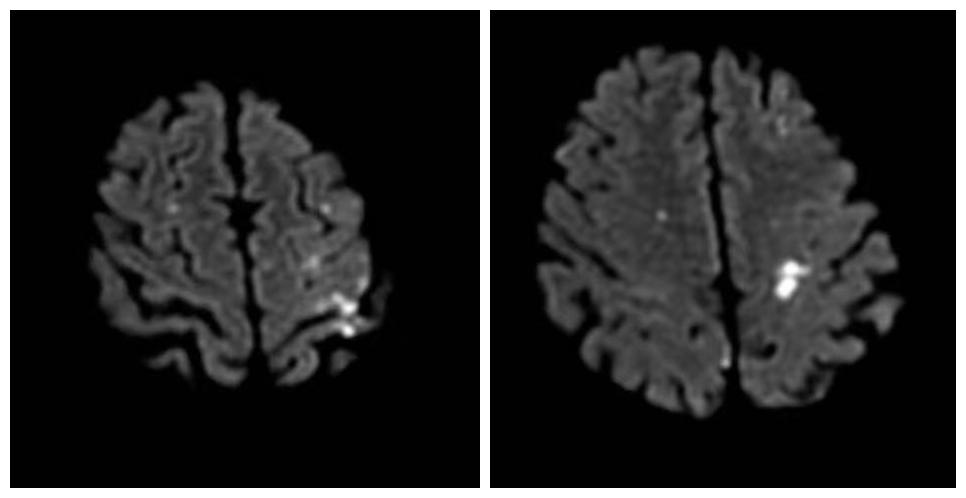

经过磁共振检查, 神经内科季新发主任 诊断:老人患有多发性脑梗死。进一步头颈部CTA检查,发现老人双侧椎动脉闭塞、颈动脉重度狭窄。

磁共振检查图:白色明亮处为脑梗处